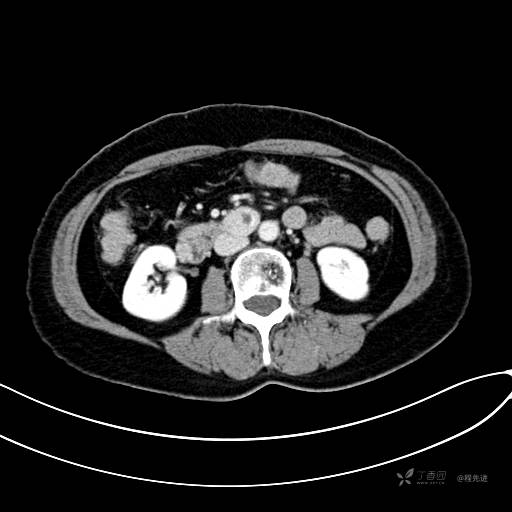

CT增强静脉期